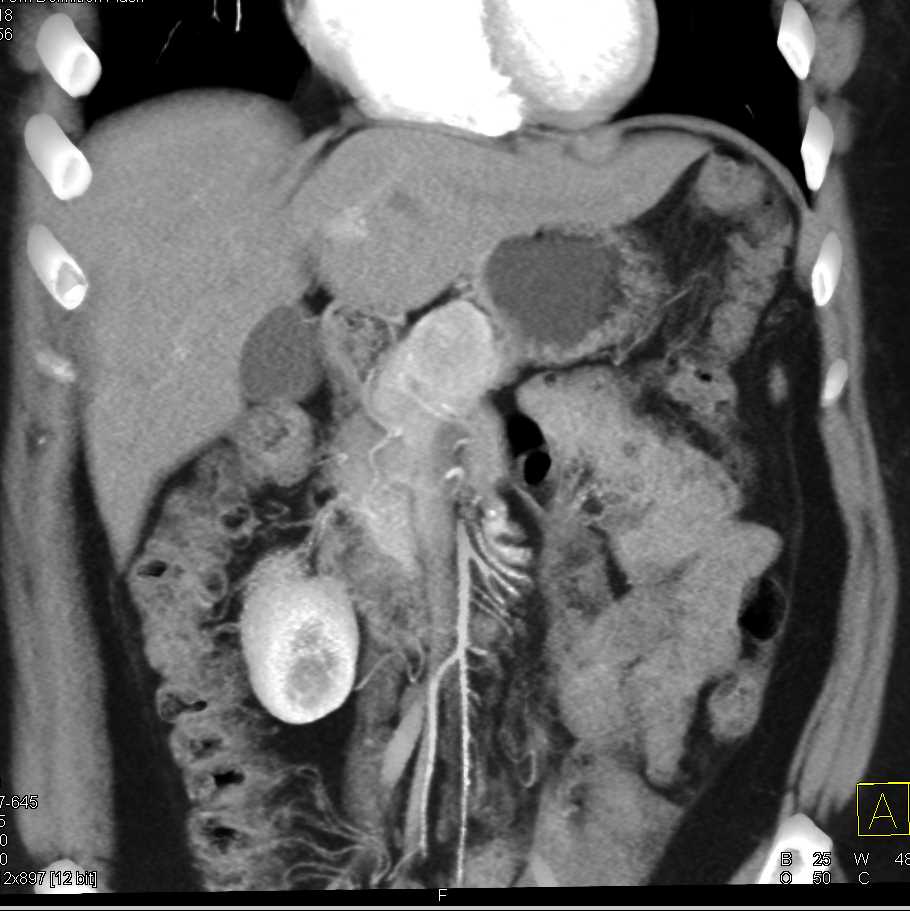

Neuroendocrine Tumor Body of Pancreas